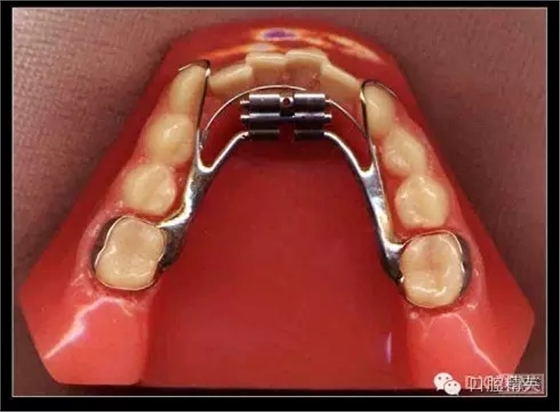

三、擴(kuò)弓器

很多牙列不齊常伴隨牙弓過窄,所以擴(kuò)弓器是正畸醫(yī)生的好伙伴,它可以以多種形態(tài)和您見面。